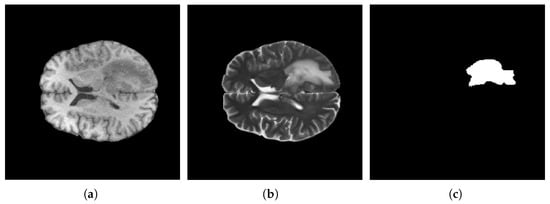

4.3. Data Prepossessing

4.4. Proposed Model